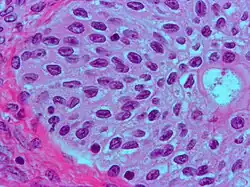

| High magnification micrograph of a Brenner tumor, a type of surface epithelial-stromal tumor. H&E stain. | |

Brenner tumor

Brenner tumors are uncommon surface-epithelial stromal cell tumors in which the epithelial cell (which defines these tumors) is a transitional cell. These are similar in appearance to bladder epithelia. The tumors may be very small to very large, and may be solid or cystic. Histologically, the tumor consists of nests of the aforementioned transitional cells within surrounding tissue that resembles normal ovary. Brenner tumors may be benign or malignant, depending on whether the tumor cells invade the surrounding tissue.